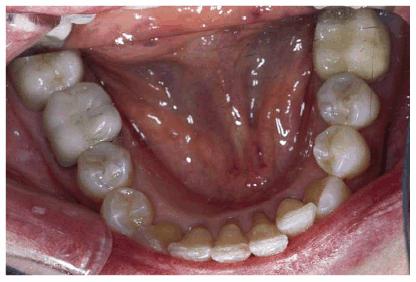

Figure 29-1K: Note the crowding of the mandibular anterior teeth.

Figure 29-1L: The teeth are less crowded, and the new tooth-colored restorations have been placed.

Figure 29-1M: The maxillary arch shows anterior crowding and defective amalgam restorations.

Figure 29-1N: Following 12 months of orthodontic treatment, the patient's amalgam restorations were replaced with posterior composite resin.

Figure 29-1O: Interdisciplinary 949o141j therapy including orthodontics, periodontics, and restorative dentistry combined to produce this attractive result 2 years following the initiation of treatment in this now younger-looking 78-year-old lady.